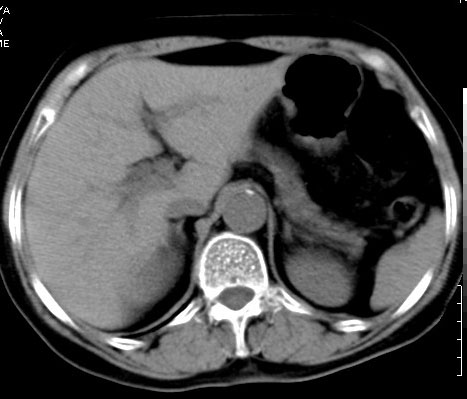

患者,女,70岁,外院查体发现肾占位,无症状.化验(-)。

以下是平扫: